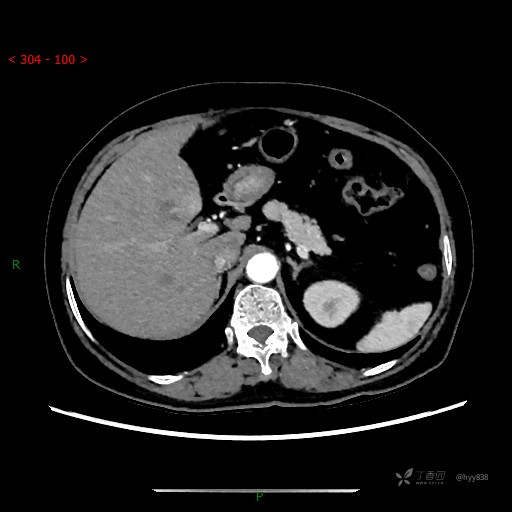

静脉期